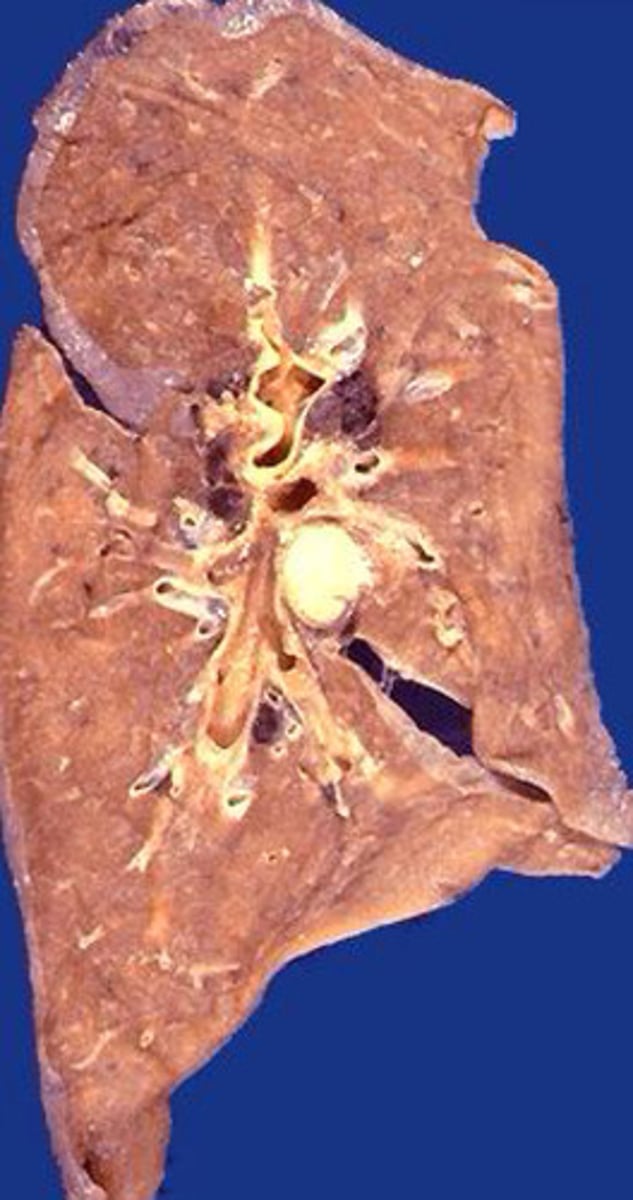

Caceous necrosis of the lung

What kind of necrosis is shown?